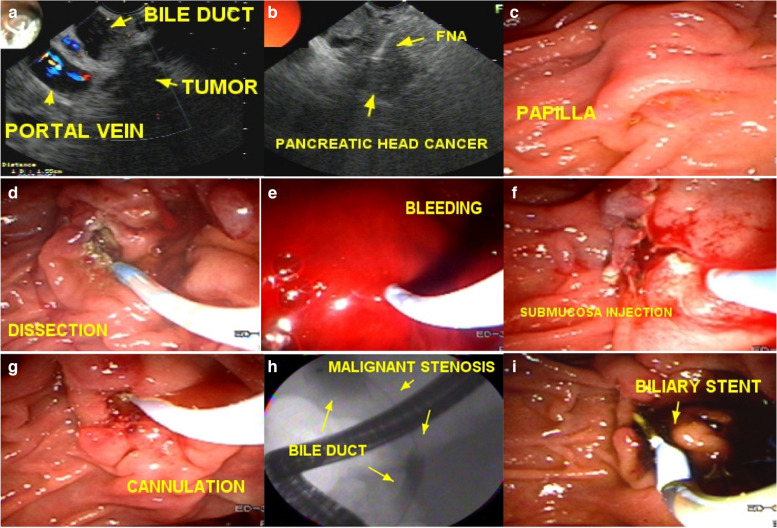

All patients had their exams previously evaluated and underwent preparation with a 12-hour fast before the procedure. Patients who were using antiplatelet agents and anticoagulants were instructed to discontinue these medications. The use of ciprofloxacin 500 mg every 12 hours was indicated for all patients, starting from 6 hours when there was no increase in bilirubin and 24 hours previously in cases of bile duct obstruction in patients with elevated bilirubin levels. All patients were initially submitted to the standard cannulation technique, using the 3-way sphincterotome and 0.035 or 0.025 guide wire, depending on the availability of the brands Olympus®, Boston®, Cook®, MediGlobe®, Scitech® or GFE®. The WEM® electrosurgical generator, model SS200A, was used in all cases. In the case of cannulation failure, following the criteria for indicating early fistulotomy, the patients underwent EFP. After cannulation failure (defined as failing to introduce the guide wire into the bile duct five times, even after injecting a small amount of contrast into the papilla ostium, or the guide wire inadvertently being directed into the pancreatic duct), our preference was to perform EFP early, avoiding trauma to the papilla and the injection too much contrast (Fig. 1).

After identification and “palpation” with the tip of the fistulotome of the lateral limits of the papilla and exposure of the infundibulum, a wide, shallow incision only of the papillary mucosa was iniciated and, purely cut, with the fistulotome needle adjusted to approximately 2 mm, from top to bottom, just below the transverse crease, avoiding opening the region of the common channel. With the needle-knife, the needle was retracted, and the mucosal edges were pushed aside to expose the submucosa. Lateral incisions were made to expand the exposure and then superficial incisions were made to open the submucosa and, dissect thin layers one at a time, interspersed by blunt dissection with the tip of the needle-knife retracted; these steps were followed by identification of vessels, hemostasis and exposure of the sphincter muscle of the distal common bile duct. If bleeding occured, washing was performed with pressurized water through the fistulotome catheter itself or through the working channel of the duodenoscope, the bleeding point was identified and captured with hot biopsy forceps and sealed by seizure, rapid hemostasis was achieved by coagulation, and underlying thermal tissue damage was avoided. At this stage, transversal accessory incisions were made to remove the mucosa over the papilla and improve exposure (Fig. 2).

Subsequently, sectioning of the muscle fibers and of the common bile duct mucosa was performed, with bile outflow in most cases. Once the common bile duct mucosa was identified, the guide wire was introduced, confirmed by radioscopy and bile duct contrast (Fig. 3) (video 1).